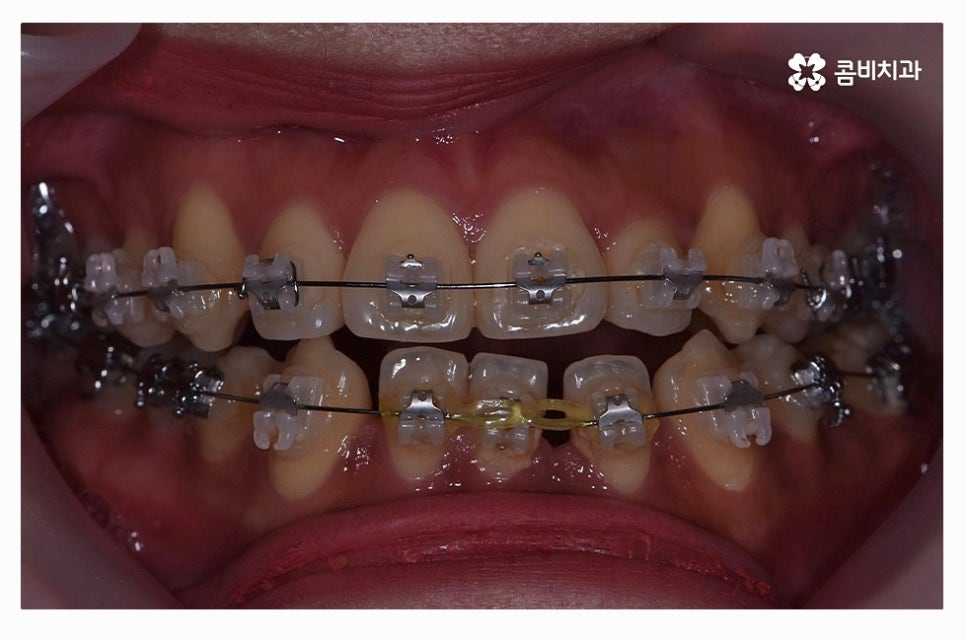

치아교정은 장기간의 치료 계획을 세워야 하기 때문에

교정 효율성이 좋고, 상대적으로 통증이 적으며 관리가 편리한

클리피씨 장치가 보편적으로 많이 활용되고 있으며

치열 상태나 환자의 니즈에 따라서 심미성이 높은 설측교정이나

투명교정이 활용되는 경우도 있어요.